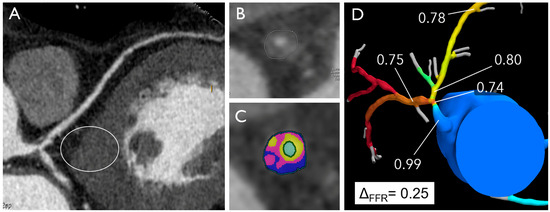

- Lee, J.M.; Choi, G.; Koo, B.K.; Hwang, D.; Park, J.; Zhang, J.; Kim, K.J.; Tong, Y.; Kim, H.J.; Grady, L.; et al. Identification of High-Risk Plaques Destined to Cause Acute Coronary Syndrome Using Coronary Computed Tomographic Angiography and Computational Fluid Dynamics. JACC Cardiovasc. Imaging 2019, 12, 1032–1043. [Google Scholar] [CrossRef] [PubMed]

- Andreini, D.; Collet, C.; Leipsic, J.; Nieman, K.; Bittencurt, M.; De Mey, J.; Buls, N.; Onuma, Y.; Mushtaq, S.; Conte, E.; et al. Pre-procedural planning of coronary revascularization by cardiac computed tomography: An expert consensus document of the Society of Cardiovascular Computed Tomography. J. Cardiovasc. Comput. Tomogr. 2022, 16, 558–572. [Google Scholar] [CrossRef] [PubMed]